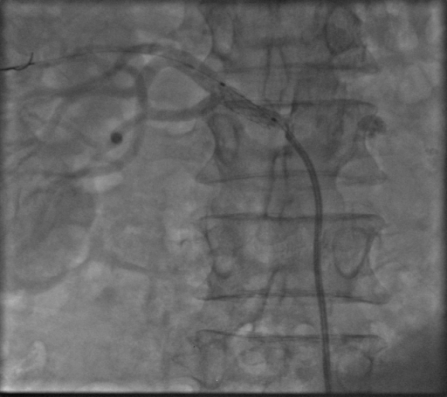

患者女性,57岁,突发上腹疼痛伴呕血,在pilipili 住院后经止血、补液等对症治疗,呕血仍没得到完全控制,血色素持续降低,行急诊胃镜提示消化道溃疡并出血,经多学科会诊后,认为应以介入手段进行腹腔动脉造影+备出血动脉栓塞术。经刘稳棠医生细心沟通及讲解手术方案,积极与患者及家属沟通并取得同意后,立即通知介入室行急诊介入止血治疗。

术中造影发现胃十二指肠一分支动脉渗血,随后应用栓塞剂进行栓塞,造影复查出血动脉未见显示,止血成功。术后患者症状改善,未再出现呕血、血色素上升,生命体征平稳。